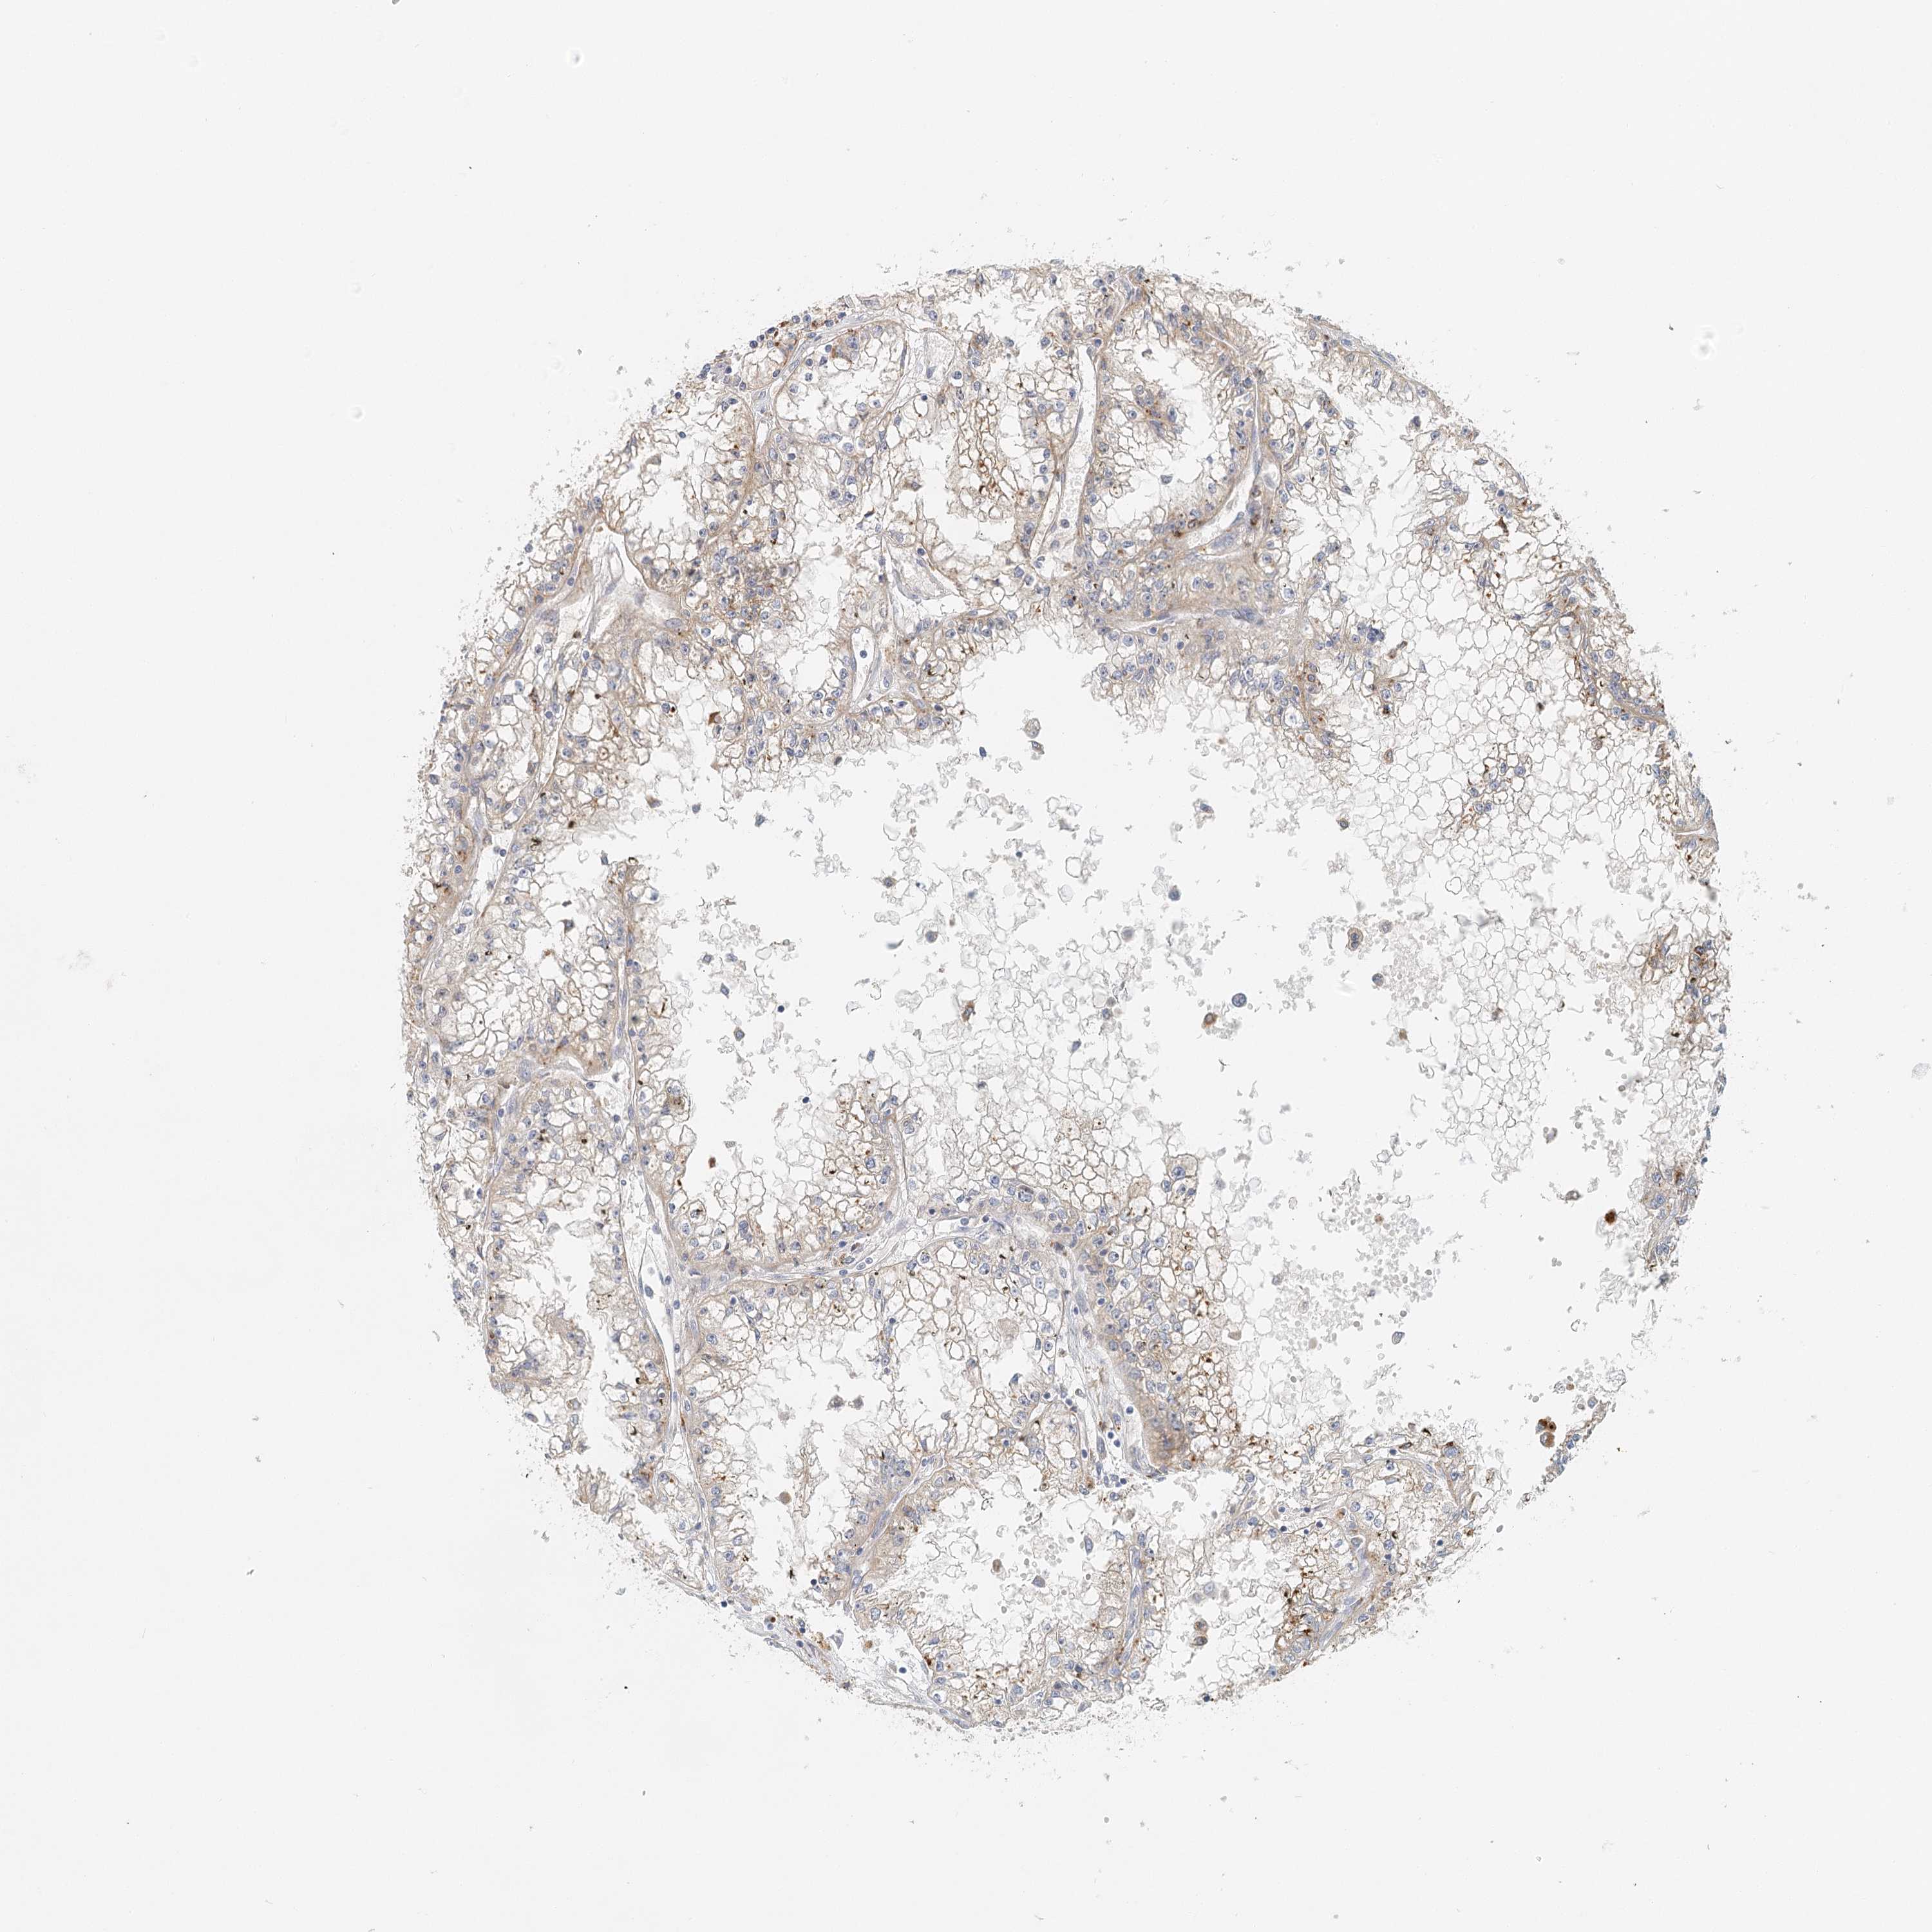

KIDNEY RENAL CLEAR CELL CARCINOMA (VALIDATION) - Interactive survival scatter ploti

VSIG1 is not prognostic in Kidney Renal Clear Cell Carcinoma (validation)

: 3.72

Average pTPM 2.7

Number of samples 100